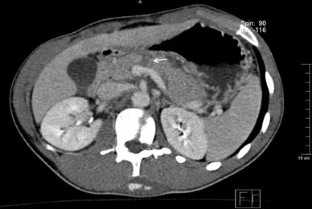

Eleven patients (2 with grade I injury, 3 with grade II injury, and 6 with grade III injury, all diagnosed by contrast-enhanced helical CT) were included. Nonsurgical management was carried out in all of these patients. Among grade III patients, one developed a peripancreatic abscess; another, a pancreatic fistula. Both were successfully treated nonoperatively. The average length of hospital stay was similar in grade I-II and grade III patients. After a median follow-up of 57 months no mortality or pancreatic sequelae had occurred.

Fig. 1